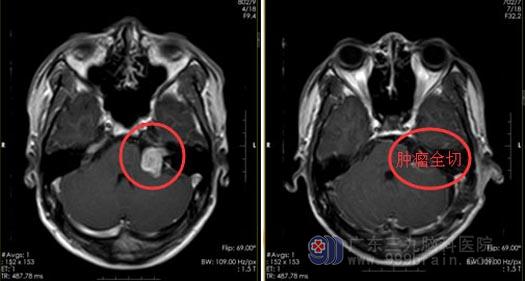

一年时间后,耳鸣开始影响小叶的生活,白天和晚上都无法入睡,家人这才带着他在当地医院检查,头颅CT检查结果:左侧桥小脑角区斑块等密度影,性质待定。广东三九脑科医院进一步MR检查提示:左侧桥小脑角区占位性病变并突入邻近左侧内听道内,考虑听神经瘤,病变范围约1.6cm×2.2cm×2.1cm。

经家属同意后,由鲁明副院长主刀在全麻下行“左侧桥小脑角肿瘤切除+硬脑膜修补+颅骨成形术”,术中见左侧听神经、面神经位于肿瘤前下方,经分离面神经保留完整,三叉神经、舌咽神经受肿瘤压迫明显,经细心分离完整保留,显微镜下电凝分块将肿瘤全切除。

术后,小叶恢复良好。术后病理:左侧桥小脑角神经鞘瘤。